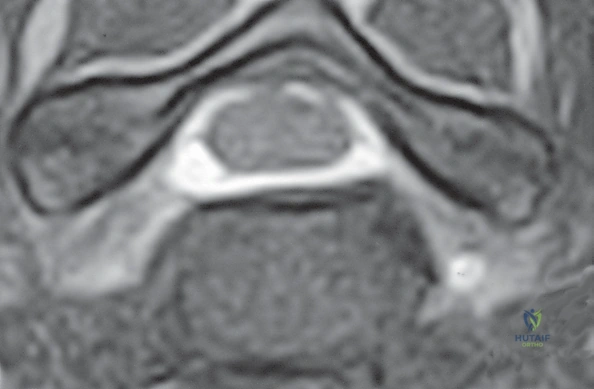

- التصوير بالرنين المغناطيسي (MRI): وهو الفحص الأهم لتحديد موقع الانزلاق الغضروفي بدقة ومدى انضغاط الأعصاب.

1. الانزلاق الغضروفي العنقي (Cervical Herniated Disc)

يحدث عندما تتمزق الحلقة الليفية الخارجية للقرص، مما يسمح للمادة الهلامية الداخلية (النواة اللبية) بالبروز والضغط المباشر على العصب الشوكي المجاور أو الحبل الشوكي نفسه.

هذه هي المرحلة الأهم والأكثر حساسية. يقوم الجراح بإزالة أي نتوءات عظمية (Osteophytes) أو أجزاء من الغضروف الممزق التي تضغط على الأعصاب الشوكية أو الحبل الشوكي، مما يعيد للقناة الشوكية اتساعها الطبيعي.